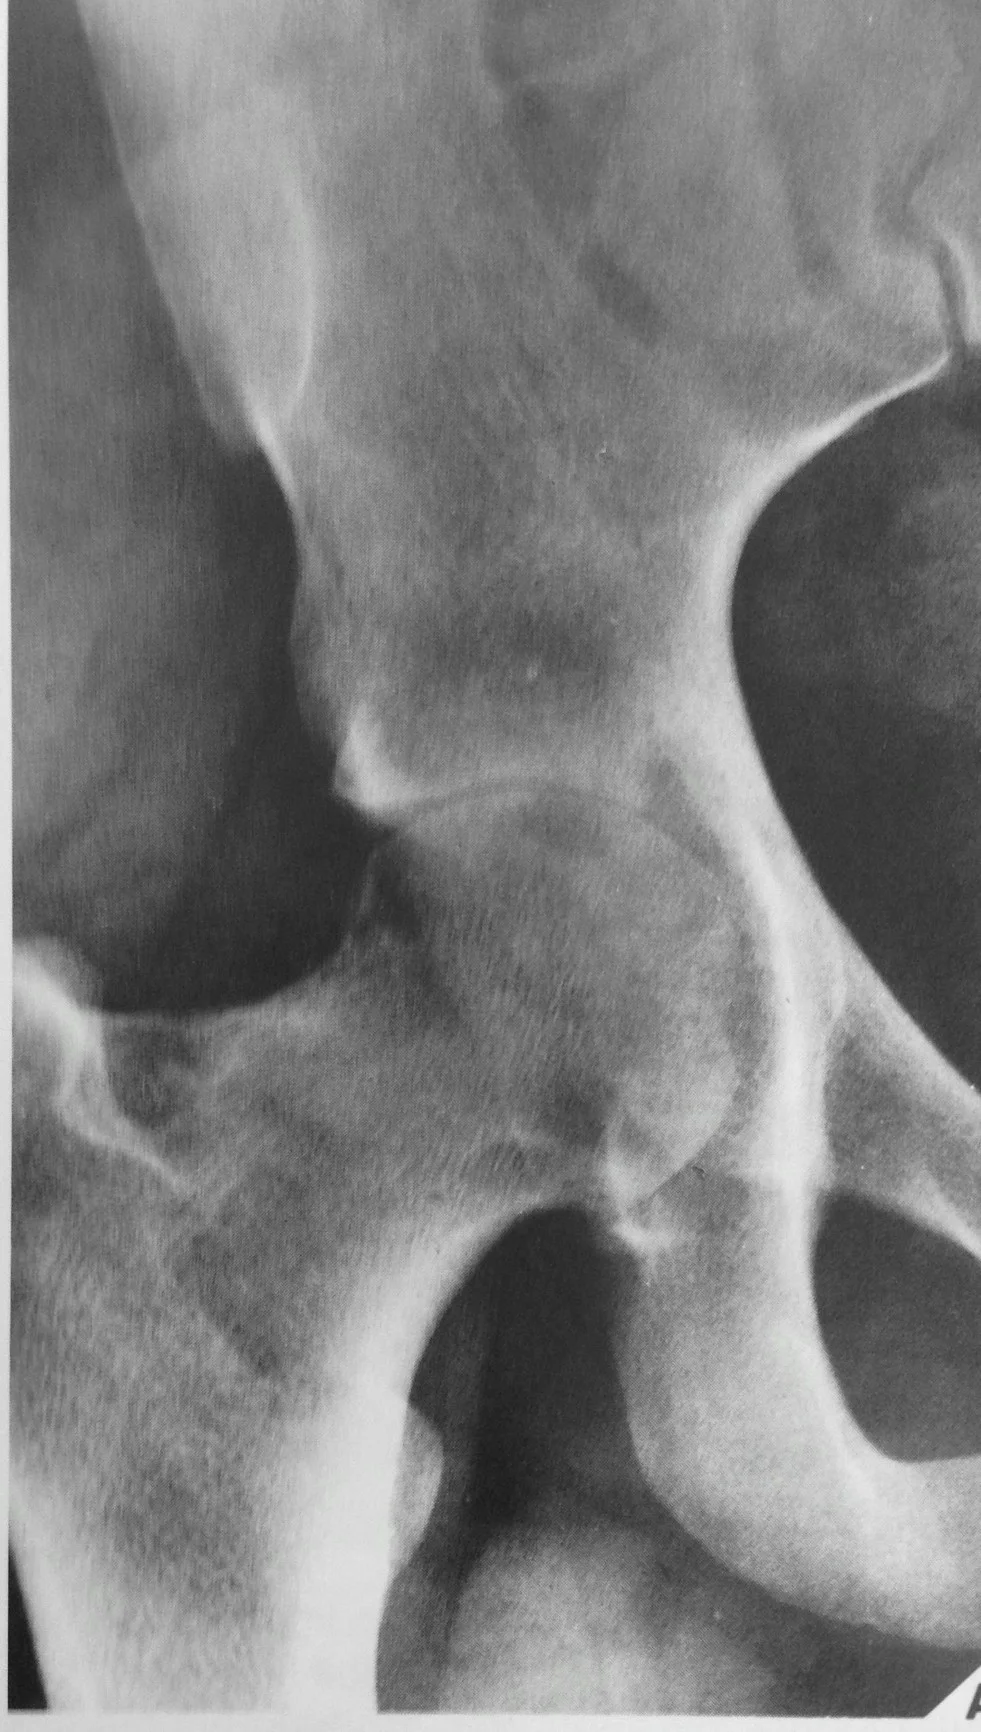

- Joints: usually monoarticular

- Peri-articular osteopenia

- Subchondral and peripheral erosions affecting both sides of the joint

- Loss of joint space